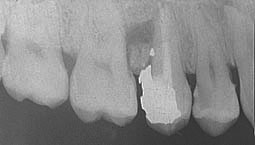

L'examen radiologique montre (Fig. 3) :

- une obturation coronaire de la 25,

- des canaux radiculaires alésés mais non obturés de la 25,

- un séquestre osseux bien délimité au niveau du septum interdentaire entre la 25 et la 26.